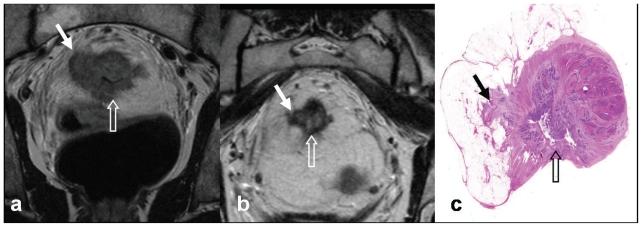

The benefit of neoadjuvant therapy for tumours above the peritoneal reflection is not clear. The purpose of this study is to demonstrate the feasibility and downstaging of treating locally advanced tumours from high rectum to distal sigmoid with preoperative chemoradiotherapy (CRT).

Seventeen patients with high rectal, rectosigmoid or distal sigmoid tumours above the peritoneal reflection received neoadjuvant CRT, selected on MRI findings indicating T4 disease or threatened circumferential resection margin. All patients were administered neoadjuvant chemotherapy, with Oxaliplatin or Mitomycin C and a Fluoropyrimidine. The pelvis received long-course CT-planned conformal RT, 45 Gy in 25 fractions, with a boost of 5.4-9 Gy in 3-5 fractions. Thirteen patients were treated with concomitant oral or intravenous Fluoropyrimidine chemotherapy.

Median follow-up was 37 months. Overall survival was 82.35% (95% Confidence Interval (CI) 54.7-93.9) and disease free survival 81.25% (95% CI 52.5-93.5). Only 1 patient suffered loco-regional relapse. Chemotherapy regimens were well tolerated, though some patients required dose reductions. Nine patients (52.9%) lowered pathologic disease AJCC stage, i.e. 'downstaged'. Six patients (35.3%) achieved complete pathological response. Clear margins were attained in all but 1 patient. Three patients were converted from cT4 to ypT3. No patient required a gap during CRT. One patient suffered a grade III acute toxicity, but no grade IV (RTOG). There were 3 grade III and 3 grade IV late toxicities (LENT-SOMA).

Locally advanced high rectal and recto-sigmoid tumours may be treated with pre-operative CRT with acceptable toxicity, impressive down-staging, and clear surgical margins.